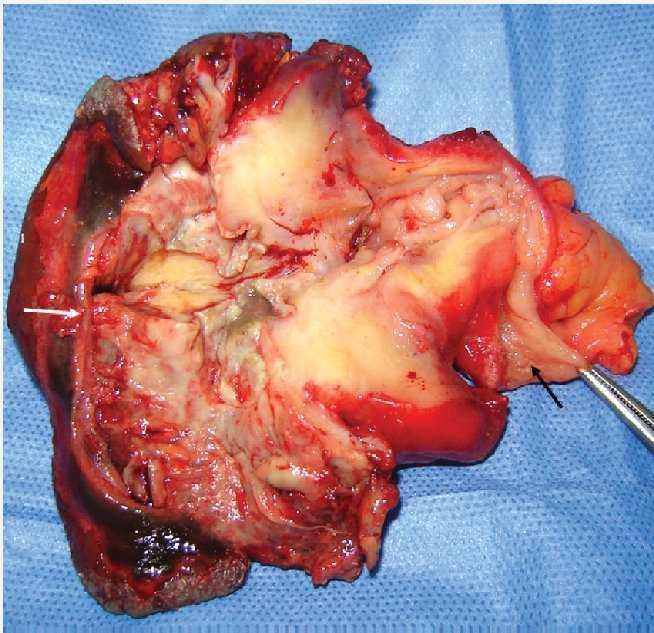

Imagen 4. Pieza quirúrgica. Base apendicular (flecha negra). Orificio cutáneo (flecha blanca).

Imagen 5. Pieza quirúrgica. Base apendicular (flecha negra). Orificio cutáneo (flecha blanca).